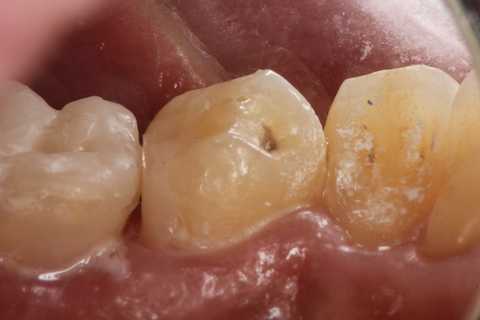

残根上のCR8 2025.10.28